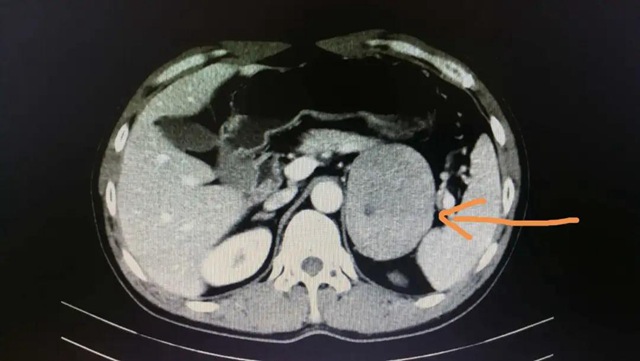

该患者,男性,52岁,因“尿频2年”住院,检查发现左侧肾上腺肿瘤(9cm)。

▲CT扫描下的肾上腺肿瘤